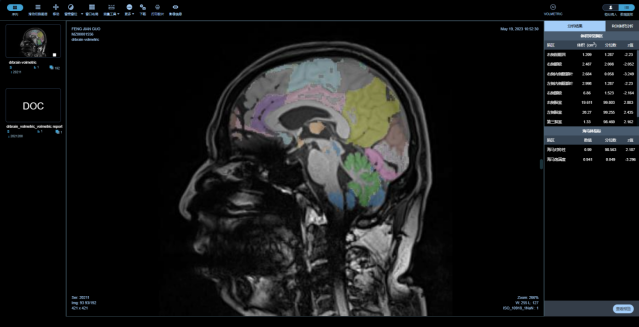

產(chǎn)品基于IWG-1(2007)、NIA-AA(2011)、2018中國癡呆與認(rèn)知障礙診斷指南、適用于中國人群的阿爾茨海默病篩查和診斷框架(2019)、阿爾茨海默病MR檢查規(guī)范中國專家共識(2019)等指南和共識、規(guī)范、方案的基礎(chǔ)上,進(jìn)行了人工智能(AI)醫(yī)療技術(shù)創(chuàng)新。2018中國癡呆與認(rèn)知障礙診斷指南中指出,神經(jīng)影像學(xué)是排除其他可治療性癡呆,輔助臨床各種癡呆的診斷及鑒別的重要手段。結(jié)構(gòu)核磁首先是除外可治疾病,如腦腫瘤、正常顱壓性腦積水,再次是顯示AD相關(guān)的特意結(jié)構(gòu)的改變,如內(nèi)側(cè)顳葉,尤其是海馬和內(nèi)嗅皮層改變是結(jié)構(gòu)核磁有關(guān)AD研究最經(jīng)典的體現(xiàn)。本次產(chǎn)品正是以臨床腦結(jié)構(gòu)MRI數(shù)據(jù)為基礎(chǔ),實現(xiàn)對腦解剖結(jié)構(gòu)的顯示清晰,分辨率高,可清楚區(qū)分腦灰質(zhì)和腦白質(zhì),清晰顯示癡呆患者腦溝增寬加深、腦室擴(kuò)大的情況,并可進(jìn)行腦內(nèi)結(jié)構(gòu)(如海馬、杏仁核等)的線性、面積和體積測量。同時,腦結(jié)構(gòu)影像檢查結(jié)果的解讀依賴于整體的改變,而非單個腦區(qū),不應(yīng)忽略大腦其他區(qū)域可能發(fā)生的改變。本次產(chǎn)品中所應(yīng)用的深度學(xué)習(xí)方法敏感度特異度性能非常好的原因,在于其不僅僅納入形態(tài)學(xué)的標(biāo)志物如體積和形狀,還納入了體素、區(qū)域關(guān)聯(lián)、紋理等特征,可以更好以整體性的評估實現(xiàn)對AD的早期篩查與發(fā)現(xiàn)。這即是本次醫(yī)未醫(yī)療率先獲得中國第一張針對AD的基于磁共振人工智能輔助評估軟件三類證的核心臨床價值所在。

中樞神經(jīng)系統(tǒng)核磁影像AI診斷分析平臺

是專注在中樞神經(jīng)系統(tǒng)疾病的人工智能診斷分析平臺,基于醫(yī)未自行搭建的全年齡段中國人群全腦結(jié)構(gòu)影像數(shù)據(jù)庫,結(jié)合前沿的大數(shù)據(jù)分析和人工智能等核心技術(shù),快速、精準(zhǔn)評估全腦結(jié)構(gòu)變化、腦白質(zhì)病變、微出血灶及腦血流量等,以量化、直觀的結(jié)果,輔助臨床做出超早期的精準(zhǔn)診斷及疾病進(jìn)展預(yù)測。

最全面的分區(qū)

最全面的腦結(jié)構(gòu)分區(qū),快速獲取全腦100個精細(xì)腦區(qū)共165項指標(biāo),精度達(dá)到毫米級